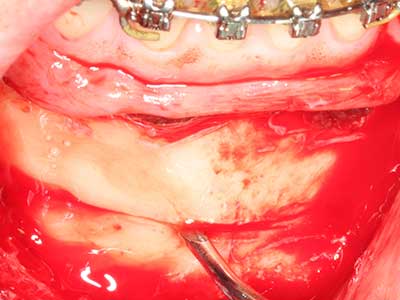

En la extracción de bloques óseos la piezocirugía también presenta ventajas adicionales: Además de la alta precisión en la osteotomía que ya se ha descrito antes, se ha comprobado que el uso de los delgados insertos de sierra resulta especialmente cuidadosas con el hueso. Frente a esto, sobre todo cuando se usan las fresas de Lindemann, cabe esperar pérdidas en la extracción significativamente más altas debido al mayor grosor de la parte frontal del cabezal (Lakshmiganthan, Gokulanathan et al. 2012). La separación basal que se necesita en particular en los injertos de bloque extraídos de forma retromolar se ve facilitada mediante sierras perpendiculares especialmente previstas a tal fin, lo que permite considerar que la cirugía piezoeléctrica es un procedimiento preciso y seguro para la obtención de bloques de hueso en el área retromolar (Happe 2007) (fig. 1-12).

El tejido óseo no solo tiene un contenido puramente mineral, sino que también presenta una importante proporción de fibras de colágeno. Esto no solo garantiza una buena resistencia a la presión, sino también una cierta flexibilidad, que puede aprovecharse para la realización de aumentos. En la plastia de expansión clásica a efectos de una partición ósea, la cresta maxilar atrofiada se divide en su eje longitudinal y, tras alcanzar una profundidad de osteotomía suficiente, se extiende con cuidado (fig. 13-16), en un caso ideal sin desperiostizar de forma visible el maxilar (Brugnami, Caiazzo et al. 2014, Stricker, Fleiner et al. 2014). Los sistemas de tornillos y placas con distancia de expansión creciente han demostrado su eficacia para distanciar entre sí las dos tablas óseas por debajo del umbral de rotura. Por regla general, se requieren anchuras de hueso residual de al menos 3 a 4 mm (Chiapasco, Zaniboni et al. 2006) para garantizar una flexibilidad y una cobertura ósea suficientes de los implantes que van a incorporarse. En caso necesario, una osteotomía de descarga vertical unilateral o bilateral puede mejorar la flexibilidad. Como alternativa a la técnica clásica se ha descrito una combinación con otras técnicas de aumento, sobre todo en la parte bucal.

Con el uso de sierras piezoeléctricas la división se efectúa de forma especialmente cuidadosa y sin pérdidas importantes de las dimensiones, por lo que no se han encontrado diferencias significativas entre los implantes realizados en el maxilar dividido y en la cresta alveolar no deficitaria (Chiapasco, Zaniboni et al. 2006, Danza, Guidi et al. 2009). No obstante, precisamente en la partición profunda y limitada de forma local, es preciso asegurarse de que exista una adecuada irrigación por agua para evitar que se produzcan sobrecargas térmicas en las áreas de osteotomía apical.